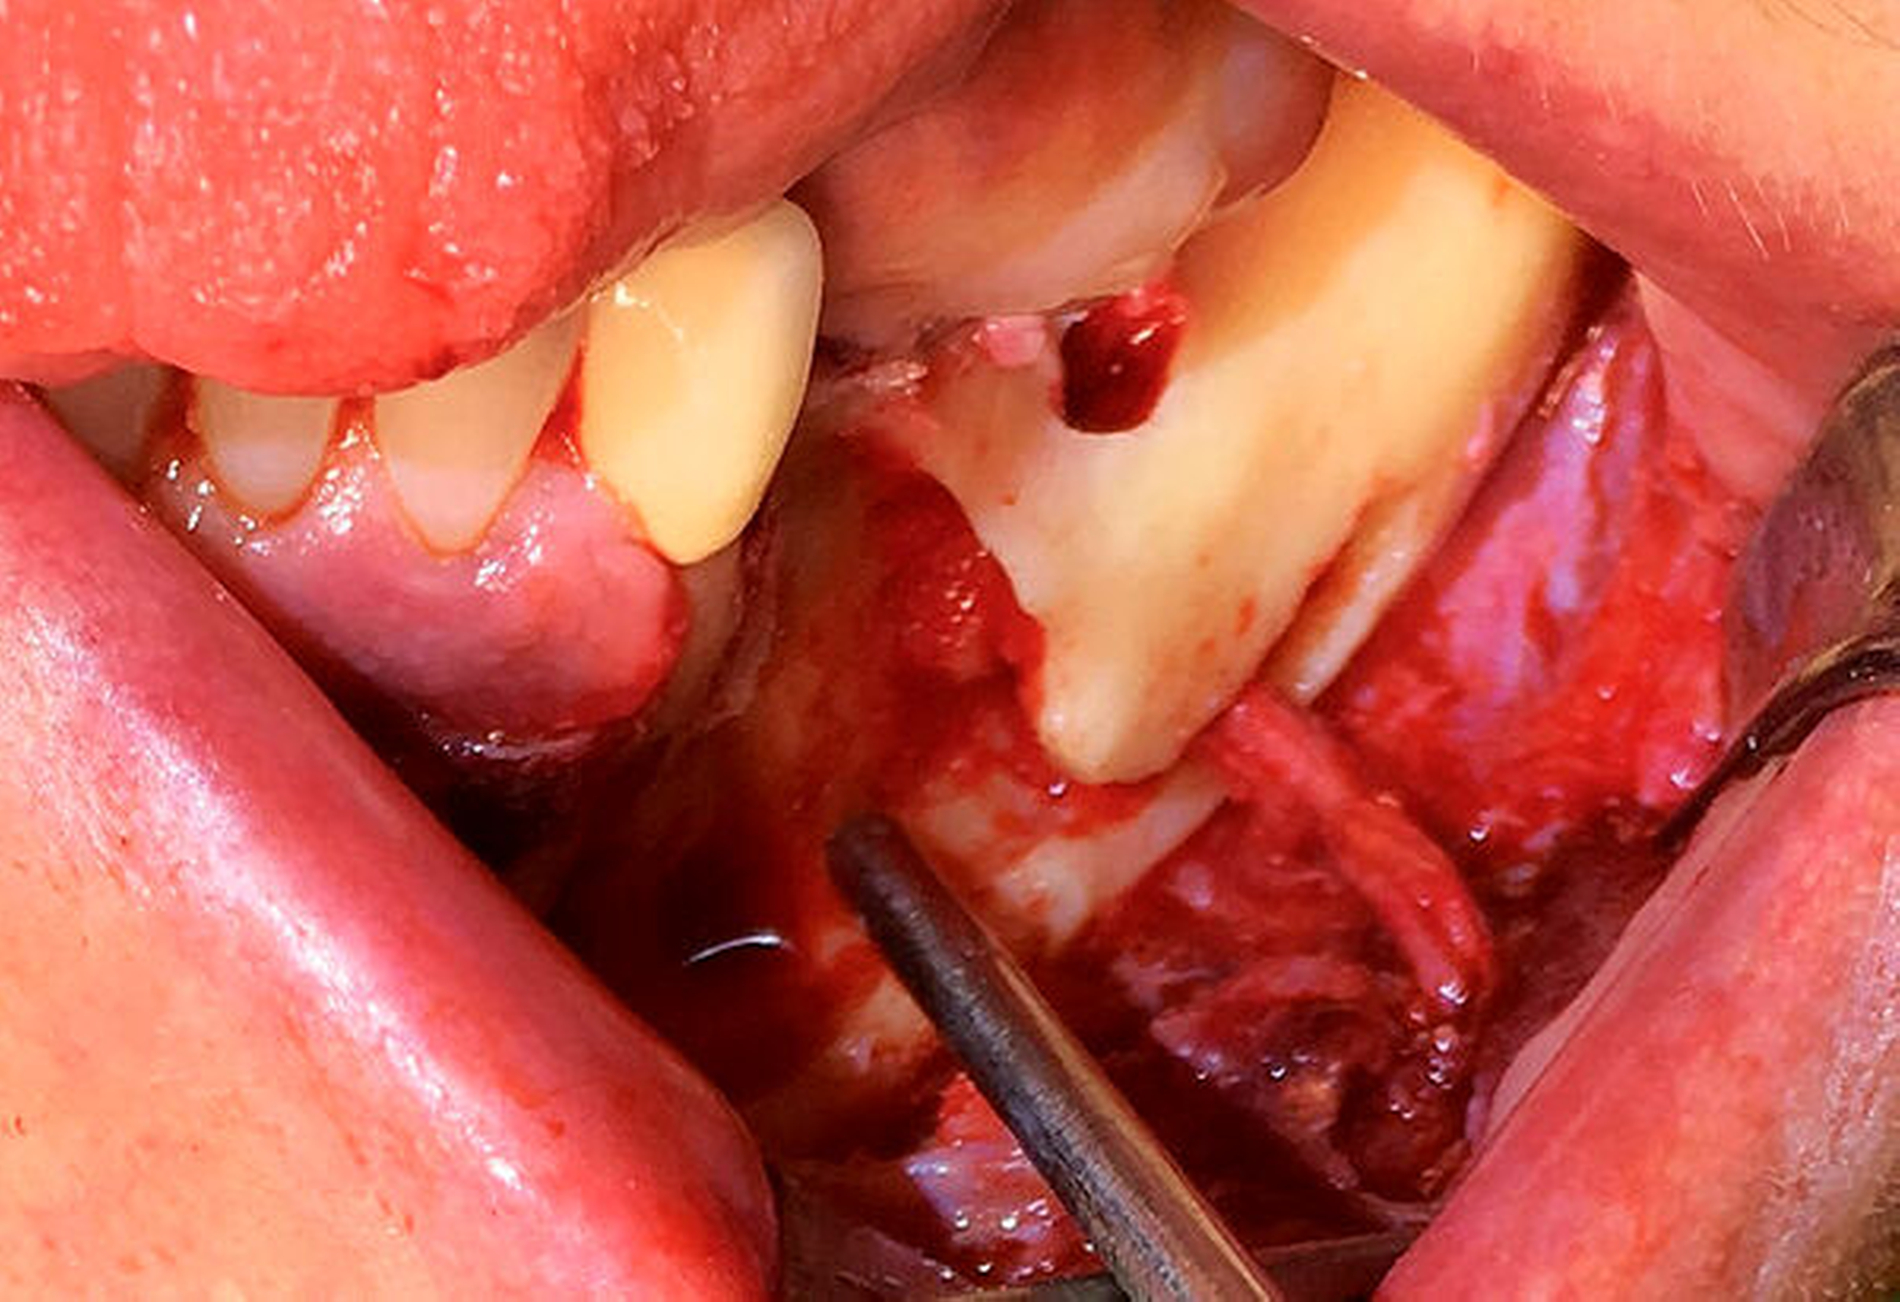

Nach der Entfernung des Wurzelrests 44 wurde der Nervus mentalis am Foramen mentale dargestellt und aus dem umgebenden Weichgewebe frei präpariert (Abbildung 6). Aus der Resektionshöhle und nach Entfernung der vestibulären Knochenlamelle auch aus dem Unterkieferkörper konnte anschließend der Sealer samt der extrem weichen Spongiosa entfernt werden. Die Lage der radiologisch dichten Verschattung im krestalen Bereich regio 36 konnte ebenfalls lokalisiert und problemlos entfernt werden. Bei dem Fremdkörper handelte es sich vermutlich um einen Amalgamrest (Abbildung 7).

Da der Sealer auch entlang des Mandibularkanals nach dorsal überpresst war, wurde zunächst eine Nervlateralisation mittels Piezosurgery durchgeführt. Nach vollständiger Freilegung des Nervs konnte der Sealer nahezu vollständig aus dem Kanal geborgen werden (Abbildung 8).